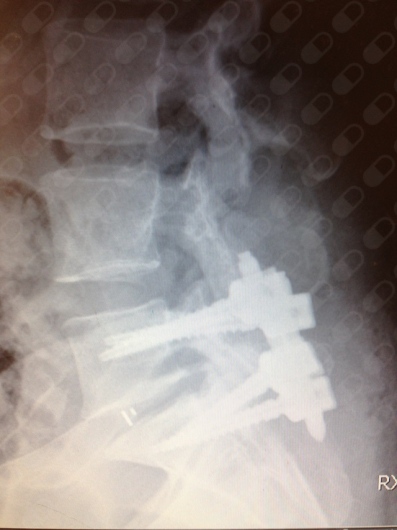

Me opero hace 12 años de la columna, donde instalo cuatro pernos y un extensor. Todo en esto lo hizo en Dipreca. Excelente profesional y atento al tratamiento post operatorio. Recomendable cien por ciento, especialista en columna.

Excelente profesional, a mi papá lo operó de la columna, después que él había tenido dos cirugías años atrás y le habían dicho que ya no podría operarse, en circunstancias que llegamos por esas casualidades de la vida al doctor González, la intervención que le hizo a mi padre fue un éxito, muy contentos con su persona y preocupación que demostró con el paciente en todo momento. Quedamos felices con su profesionalismo recomendado 100%

Me Operé con el Dr. González el 2024 de una hernia L4-L5, salió todo excelente, tuve una buena recuperación, hasta ahora no te he tenido más problemas ni dolores, es un excelente cirujano.